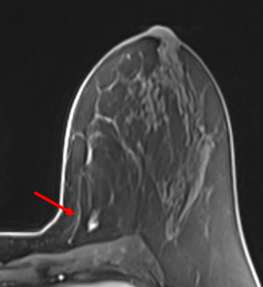

Case: LCIS Figure 2

Figure 2. Focal nonmass enhancement at site of biopsy-proven LCIS.